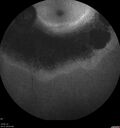

Sectoral Retinitis Pigmentosa - Asymptomatic263 views56-year-old female - The patient was in for an annual checkup because of her diabetes. No visual complaints (no night vision trouble)

293 Invitae genetic panel - negative     (0 votes)